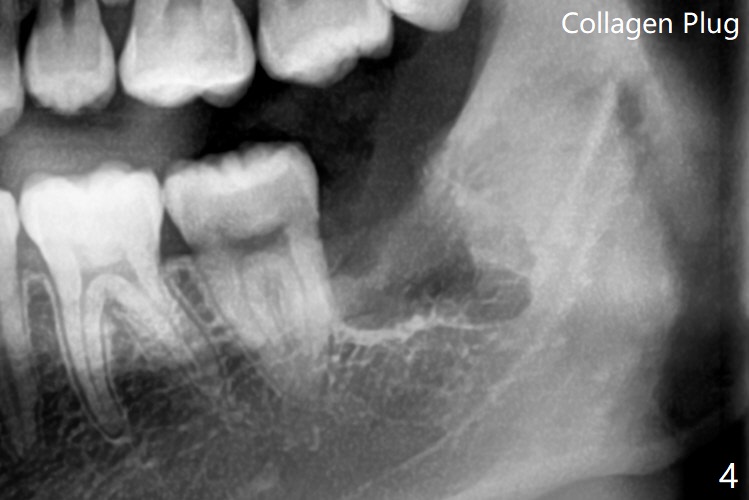

21岁男,大学毕业,即将到外州工作,害怕拔除智齿,要求拔除左下无症状智齿(图一,二)。估计智齿可能位于第二磨牙远中颊侧,切口偏近中(图三),首先在智齿近中,颊侧,远中用外科裂钻形成沟(图三:1st),插入牙挺,在保护第二磨牙前提下,挺松智齿。如果患者骨质不硬,牙挺插入处骨质形成凹陷。然后切开智齿(2nd),必要时多次切开,并记录下来。拔除后放置胶原塞(图四)。